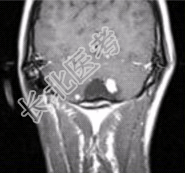

- [材料题] 男性,20岁。恶心、呕吐3d,剧烈头痛加重1d入院。MRI显示小脑下蚓部长T₁、长T₂信号影,病变可见结节状明显强化,如下图。